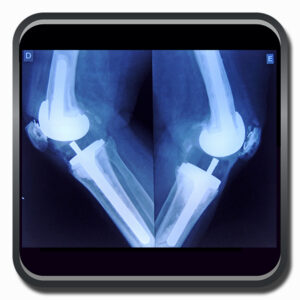

Algumas Cirurgias Complexas realizadas por profissionais da COFIB: